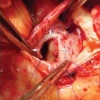

Пластика аневризмы синуса Вальсальвы

Пластическая хирургия аневризмы Вальсальвы. Коррекция врожденного расширения или выпячивания стенки аортального синуса в области полумесяцев с помощью гипсовой штукатурки стенки аорты. Пластическая хирургия аневризмы Valsalva sinus проводится в условиях гипотермии и инфракрасного хирургического доступа через аорту, правое предсердие или желудочек. Доступ через правый отдел сердца вызывает иссечение аневризмы, пластиковое покрытие хирургического дефекта или ушивание, усиленное прокладками. При трансаортальном подходе отверстие аневризмы закрывают отдельными швами или специальным патчем. При необходимости производятся пластиковые клапаны или замена протеза аортального клапана.